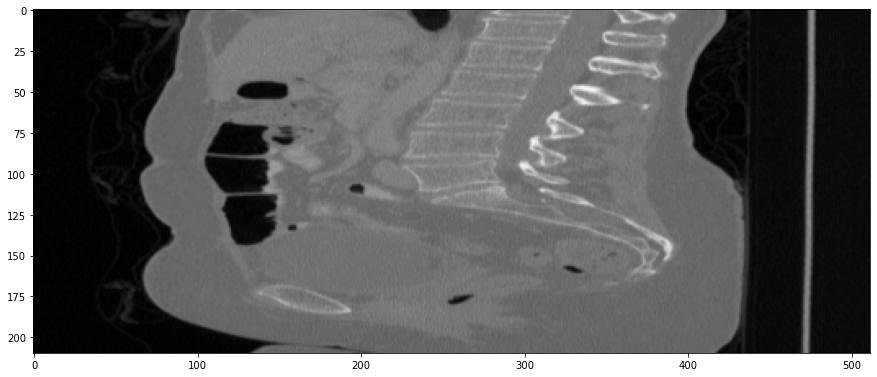

Figure 3: Coronal-plane thick-slice image quality comparison across four simulation methods.

Refer to caption

(a) True Thick-slice image

(b) Simple Averaging

RMSE: 0.0357, PSNR: 34.9781

(c) Gaussian Averaging

RMSE: 0.0454, PSNR: 32.8866

(d) Direct Downsampling

RMSE: 0.0486, PSNR: 32.2861

(e) Proposed Simulation

RMSE: 0.0070, PSNR: 49.1774

Figure 4: Sagittal-plane thick-slice image quality comparison across four simulation methods.